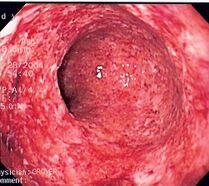

الالتهاب الحاد

الالتهاب الحاد هو أول استجابة دفاعية للجسم للإصابة أو المرض. الاستجابة تقودها الخلايا المناعية مثل العدلات والحمضات. يمكن أن يرتبط الالتهاب الحاد بالعدوى أو الإصابة الرضحية أو أمراض المناعة الذاتية (مثل التهاب المفاصل الروماتويدي) أو السرطان. على الرغم من أن الالتهاب الحاد هو جزء مهم من نظام الدفاع في الجسم، إلا أن الالتهاب الحاد المطول يمكن أن يتسبب في إصابة الأنسجة المصابة. تظهر هذه الأنواع من التغييرات بشكل شائع في الجلد والفم والجهاز الهضمي (المريء والمعدة والأمعاء الدقيقة والقولون).[5]

قد يقوم الطبيب بإزالة قطعة صغيرة من الأنسجة في إجراء يسمى الخزعة وإرسالها إلى أخصائي علم الأمراض للبحث عن التهاب حاد. من خلال فحص الأنسجة تحت المجهر، سيتمكن أخصائي علم الأمراض أيضًا من استبعاد الحالات الأخرى التي يمكن أن تبدو مثل الالتهاب مثل السرطان.